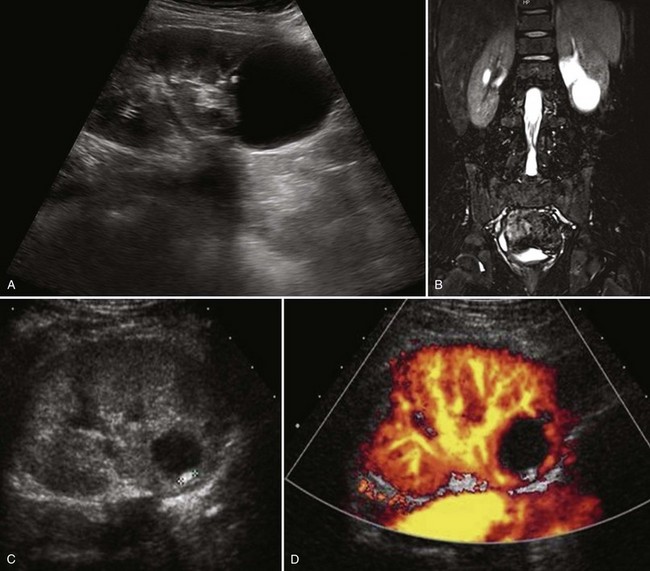

Figure 117–19 Lower pole calyceal diverticulum. A, Sagittal ultrasonogram. B, Sequence of coronal T2 images. C, Sagittal ultrasonogram shows small stone within a diverticulm. D, Color Doppler ultrasonogram demonstrates absence of flow.

(B, Courtesy of Dr. Sara Milla; C and D, courtesy of Dr. Shpetim Telegrafi.)

A localized cortical abscess draining into a calyx has also been postulated as an etiologic factor. Other proposed causes include obstruction from stones or infection within a calyx, progressive fibrosis of an infundibular stenosis, renal injury, achalasia, and spasm or dysfunction of one of the supposed sphincters surrounding a minor calyx (Amar, 1975; Patriquin et al, 1985; Siegel and McAlister, 1979). Vesicoureteral reflux has also been thought be an etiologic factor. Amar (1975) postulated that calyceal tubular backflow of infected urine could result in abscess formation and parenchymal injury leading to diverticular formation. Small diverticula are usually asymptomatic and are found incidentally by ultrasonography, CT, or MRI. These diverticula tend to progressively distend with trapped urine (Amar, 1975; Patriquin et al, 1985; Siegel and McAlister, 1979). Infection, milk of calcium (i.e., crystallization of calcium salts without actual stone formation) (Patriquin et al, 1985), or true stone formation are complications of stasis or obstruction that can produce symptoms (Lister and Singh, 1973; Siegel and McAlister, 1979) (Fig. 117–19). Hematuria, pain, and UTI may be seen in the presence of stones, which may be present in almost 40% of patients. In the Mayo Clinic series (Timmons et al, 1975), 39% of patients with calyceal diverticula had calculi.

The diagnosis is suggested on ultrasonography but confirmed on CT scan and MR urography (Ellis et al, 1990; Estrada et al, 2009) (see Fig. 117–19). Delayed films demonstrate pooling of contrast material in the diverticulum. Retrograde pyelography and delayed imaging CT with contrast medium enhancement and MR urography are used to diagnose and define the precise anatomy. Ultrasonography delineates a fluid-filled area more centrally located near the collecting system than a simple renal cyst (see Fig. 117–19). When it is filled with microcalculi, ultrasonography characteristically demonstrates a layering effect, within the diverticulum, between clear fluid above and echo-dense debris without shadowing below (Patriquin et al, 1985). Ultrasonography will image the milk of calcium within the diverticulum as the patient changes position.